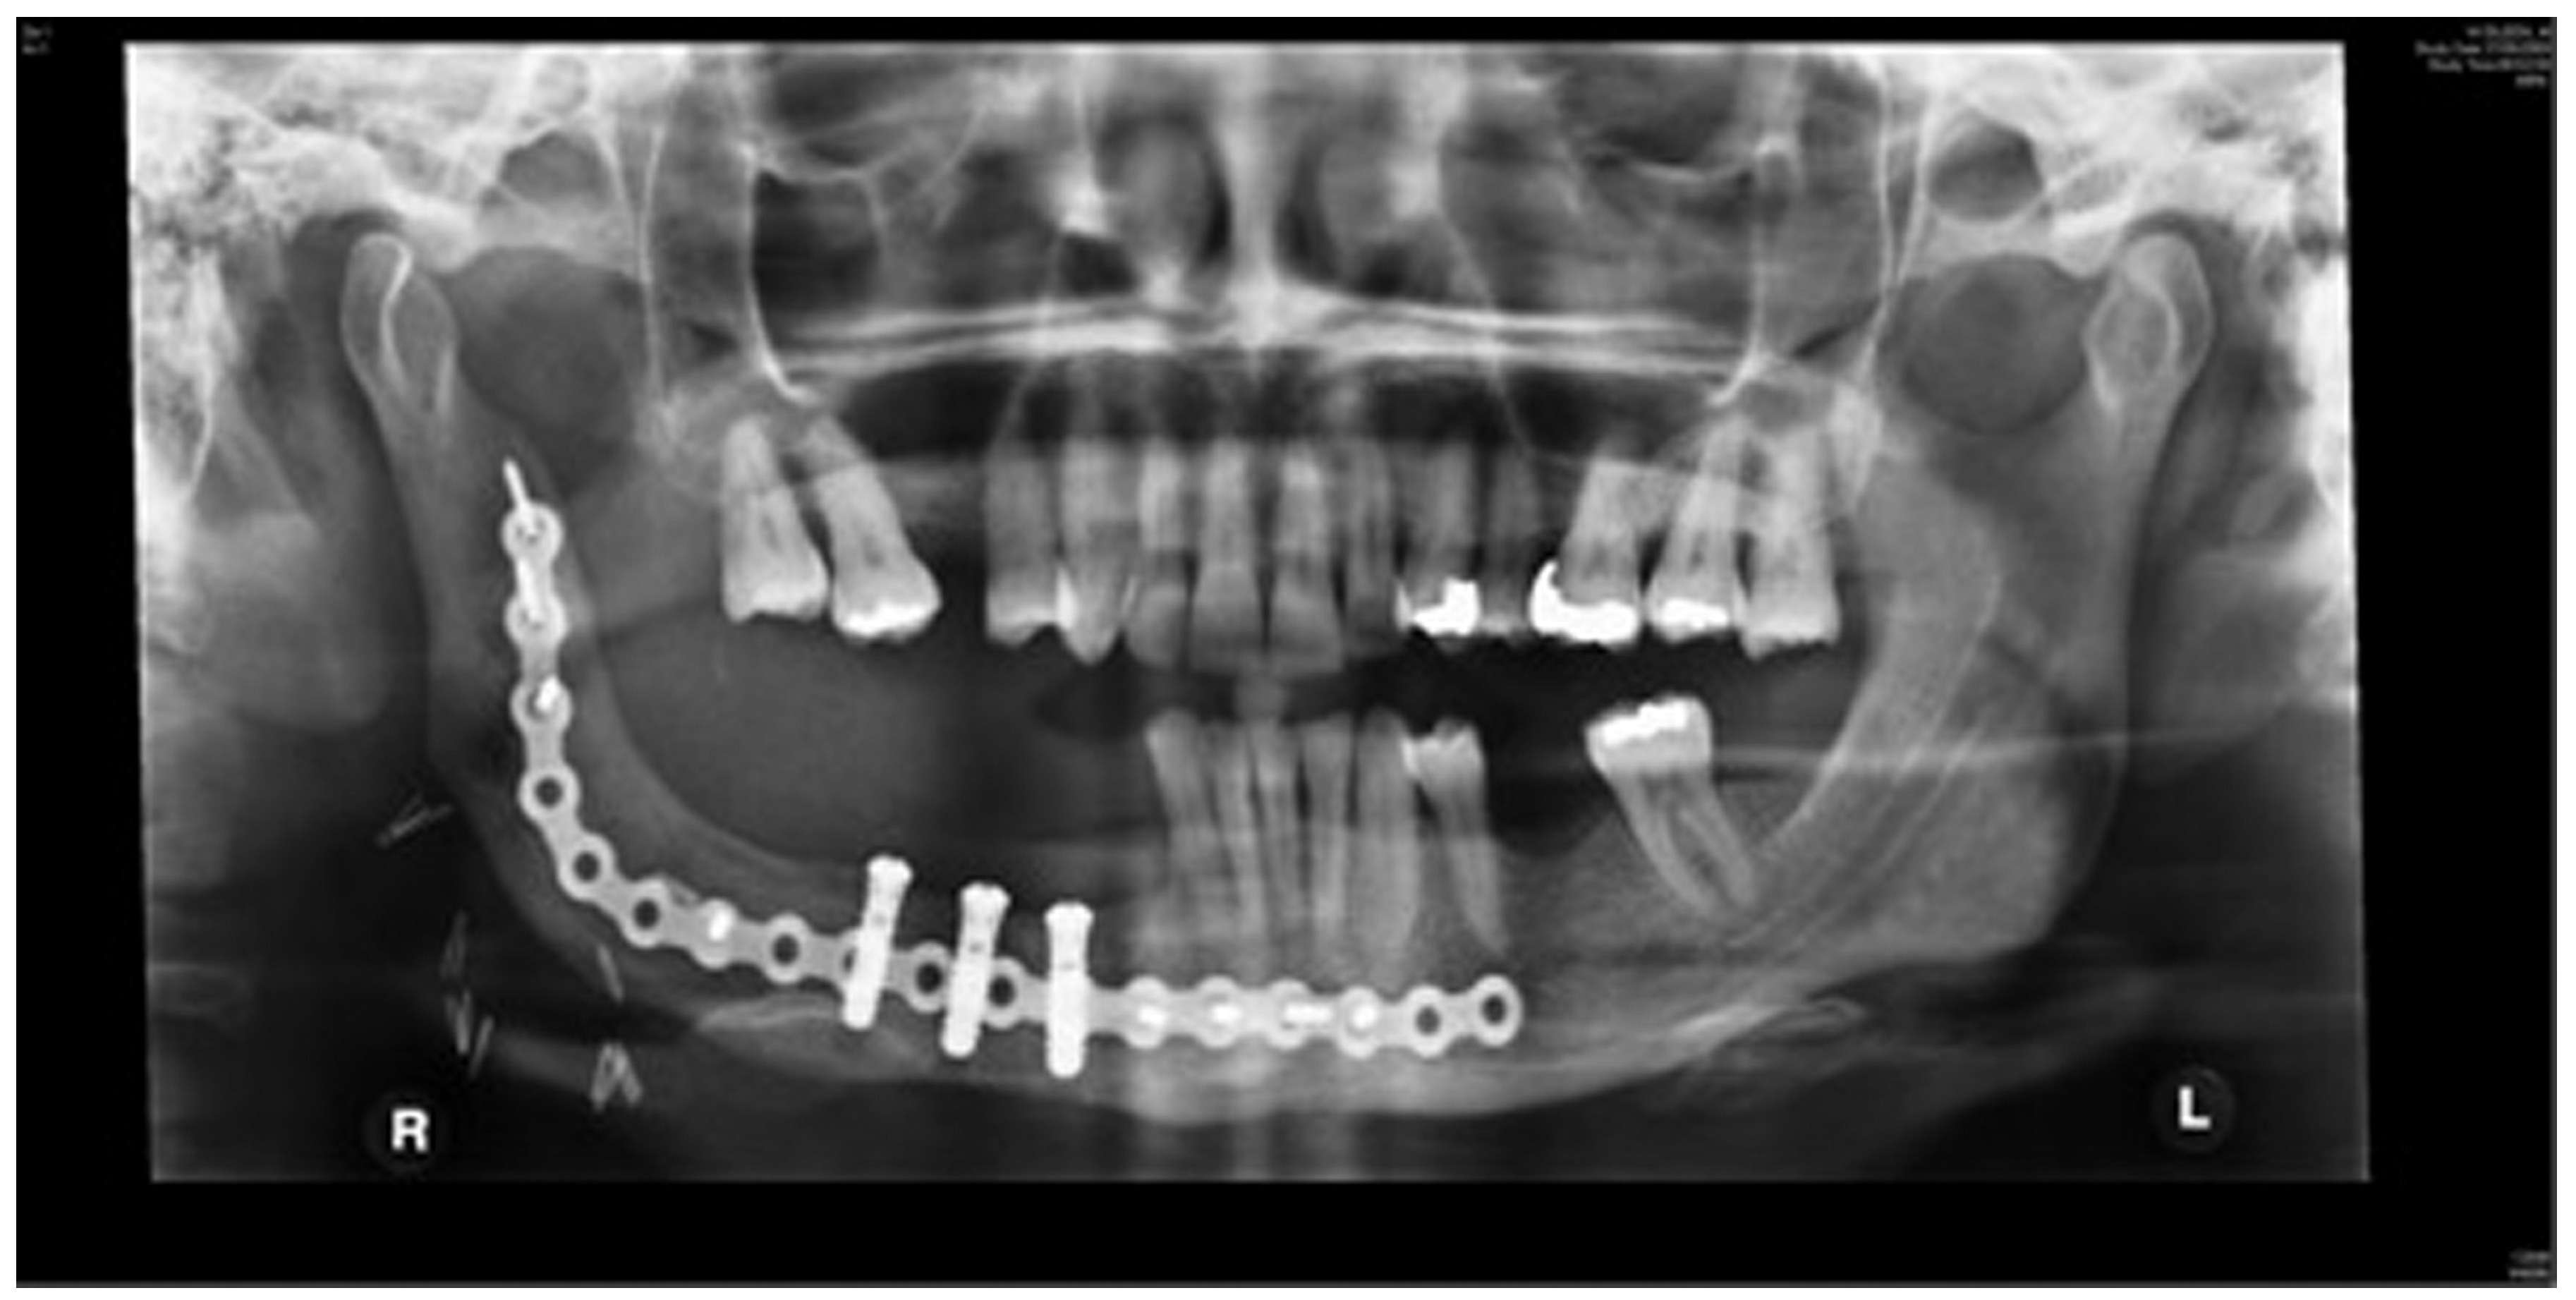

Staged reconstruction was defined as when the reconstruction with the free bone graft was performed as a secondary procedure. This secondary procedure was only performed when the oral mucosa had healed intraorally, sealing the mouth from the defect and the neck. A loadbearing locking mandibular plate was used to maintain the three-dimensional position of the bone and thus the occlusion (see Figure 1, Figure 2, Figure 3, Figure 4, Figure 5, Figure 6, Figure 7, Figure 8, Figure 9, Figure 10 and Figure 11).

Figure 2.

Resection of the mandibular tumor.

Figure 3.

Locking plate to maintain the position of the bony fragments of the mandible while the oral mucosa is healing and margins of the resected pathology awaited.

Figure 10.

Stage 1 surgery. Orthopantomography (OPT) to show locking plate to maintain the position of bony fragments whilst oral mucosa is healing in gun shot wound case.

Figure 11.

Orthopantomography(OPT) showing free bone graft placed in segmental defect.